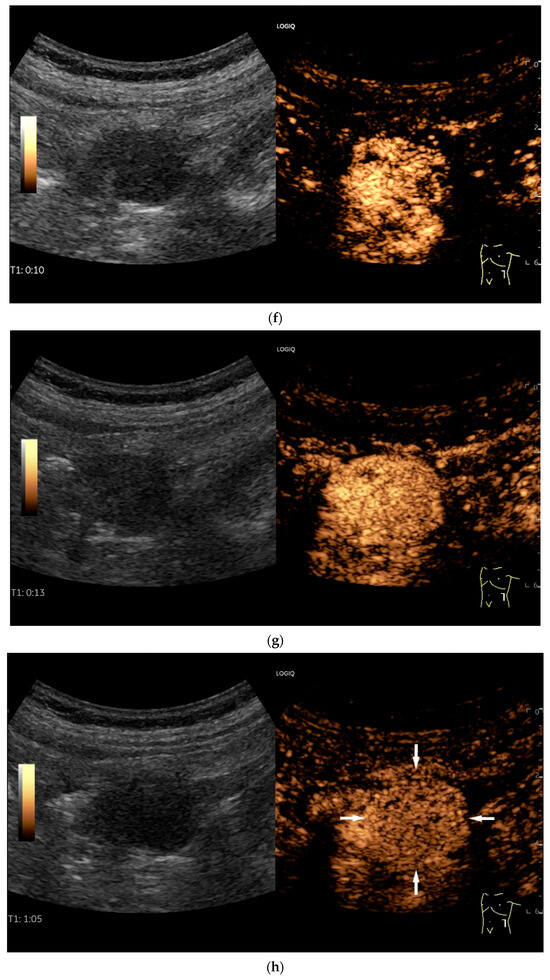

Figure 11.

GIST. A 30 mm large, very hypoechoic, almost anechoic round mass is visible in the left upper abdomen. This is located in the jejunum; the wall (W) and lumen (L) are visible (a). Macro vessels can be distinguished on Power Doppler, demonstrating that the lesion is solid and not cystic (b). On CEUS with 2.4 mL SonoVue (linear transducer 9 MHz), a small wheel-spoke-like vascular branching is visible at the margin (arrow) (c) with centrifugal enhancement (arrow) (d). Hyperenhancement is heterogeneous in the early arterial phase (e,f) and becomes homogeneous in the later course of the arterial phase (g). The extent of the heterogeneously enhanced tumor is marked with arrows (e). The intensity of the enhancement decreases during the first minute. The tumor is marked with arrows (h). Jejunal segment resection revealed the histology of an epithelioid GIST.